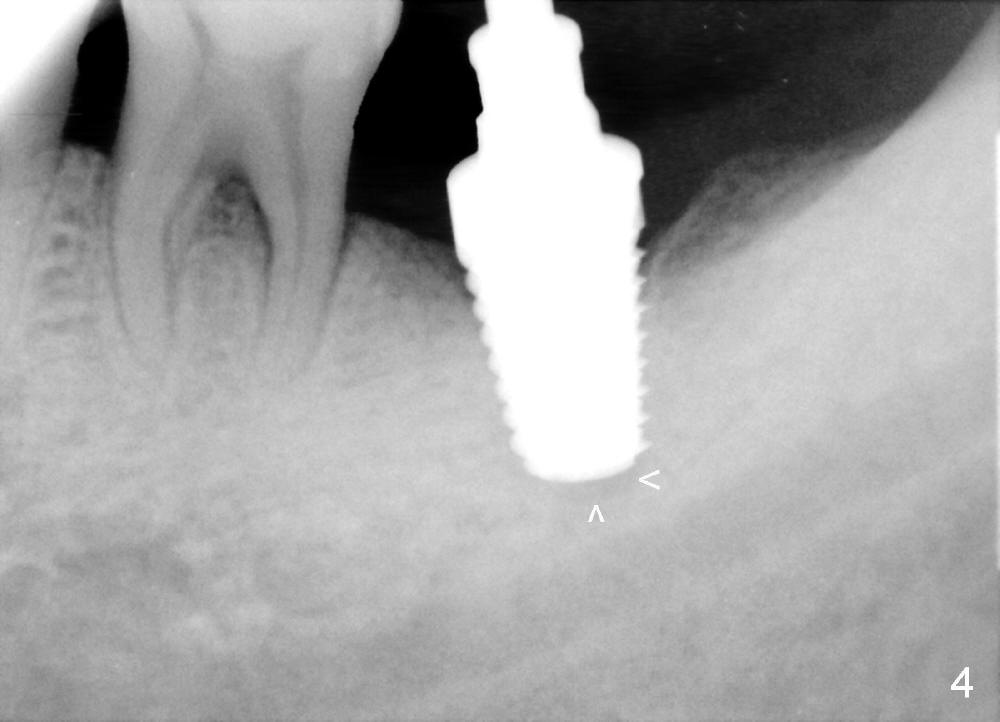

The soft tissue heals around the implant 1 months postop (Fig.1), but the implant (7x11 mm) is unstable. It should have been placed 2 mm deeper (Fig.2). It is splinted for the neighboring tooth (Fig.3). When the splint is removed 4 months later, the implant remains mobile. It is removed with infiltration anesthesia. The osteotomy is deepened by approximately 2 mm. A 7x14 mm tap is inserted with stability (Fig.4); there is apical space to be engaged further (arrowheads). A 7x14 mm implant is placed with insertion torque > 60 Ncm (Fig.5 I); an abutment (A) placed to keep perio dressing in place.